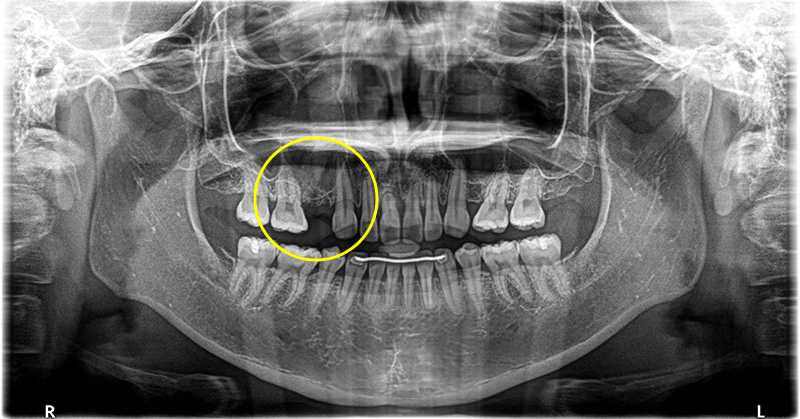

根破折で根の先端に膿がたまっているため抜歯しインプラントで修復した症例

年齢

60代

性別

女性